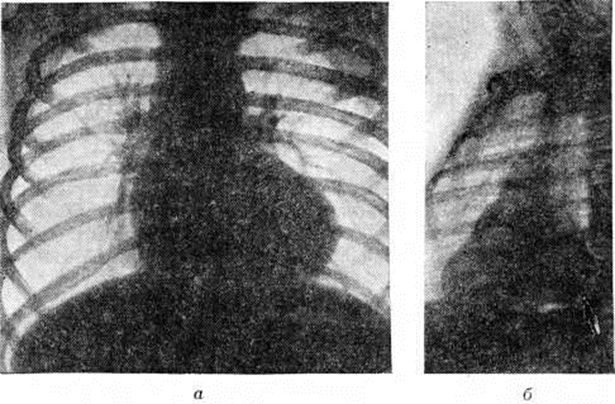

Рис. 1.

Рентгенограммы грудной клетки больного с тетрадой Фалло: а — (переднезадняя проекция) повышение прозрачности лёгочных полей и обеднение сосудистого рисунка лёгких; сердце имеет форму деревянного башмачка с закруглённой и приподнятой верхушкой, резко выраженной талией: б — (вторая косая проекция) тень левого желудочка выглядит как небольшое выбухание с крутой кривизной по задней поверхности (указана стрелкой).

Рентгенологические исследование имеет важное значение для диагностики Фалло тетрада При этом лёгочные поля имеют обеднённый артериальный сосудистый рисунок, в прикорневой зоне нередко отмечаются хаотично расположенные тени коллатеральных сосудов. Тень сердца в переднезадней проекции у большинства больных увеличена незначительно, но имеет достаточно специфическую конфигурацию, напоминающую деревянный башмачок с закруглённой, приподнятой над диафрагмой верхушкой и западением в области лёгочного ствола (рисунок 1, а). В косых проекциях выявляются признаки увеличения правых и относительное уменьшение левых отделов сердца. Тень левого желудочка во второй косой проекции выглядит как небольшое выбухание с крутой кривизной (симптом шапочки) по задней поверхности сердечной тени (рисунок 1, б).